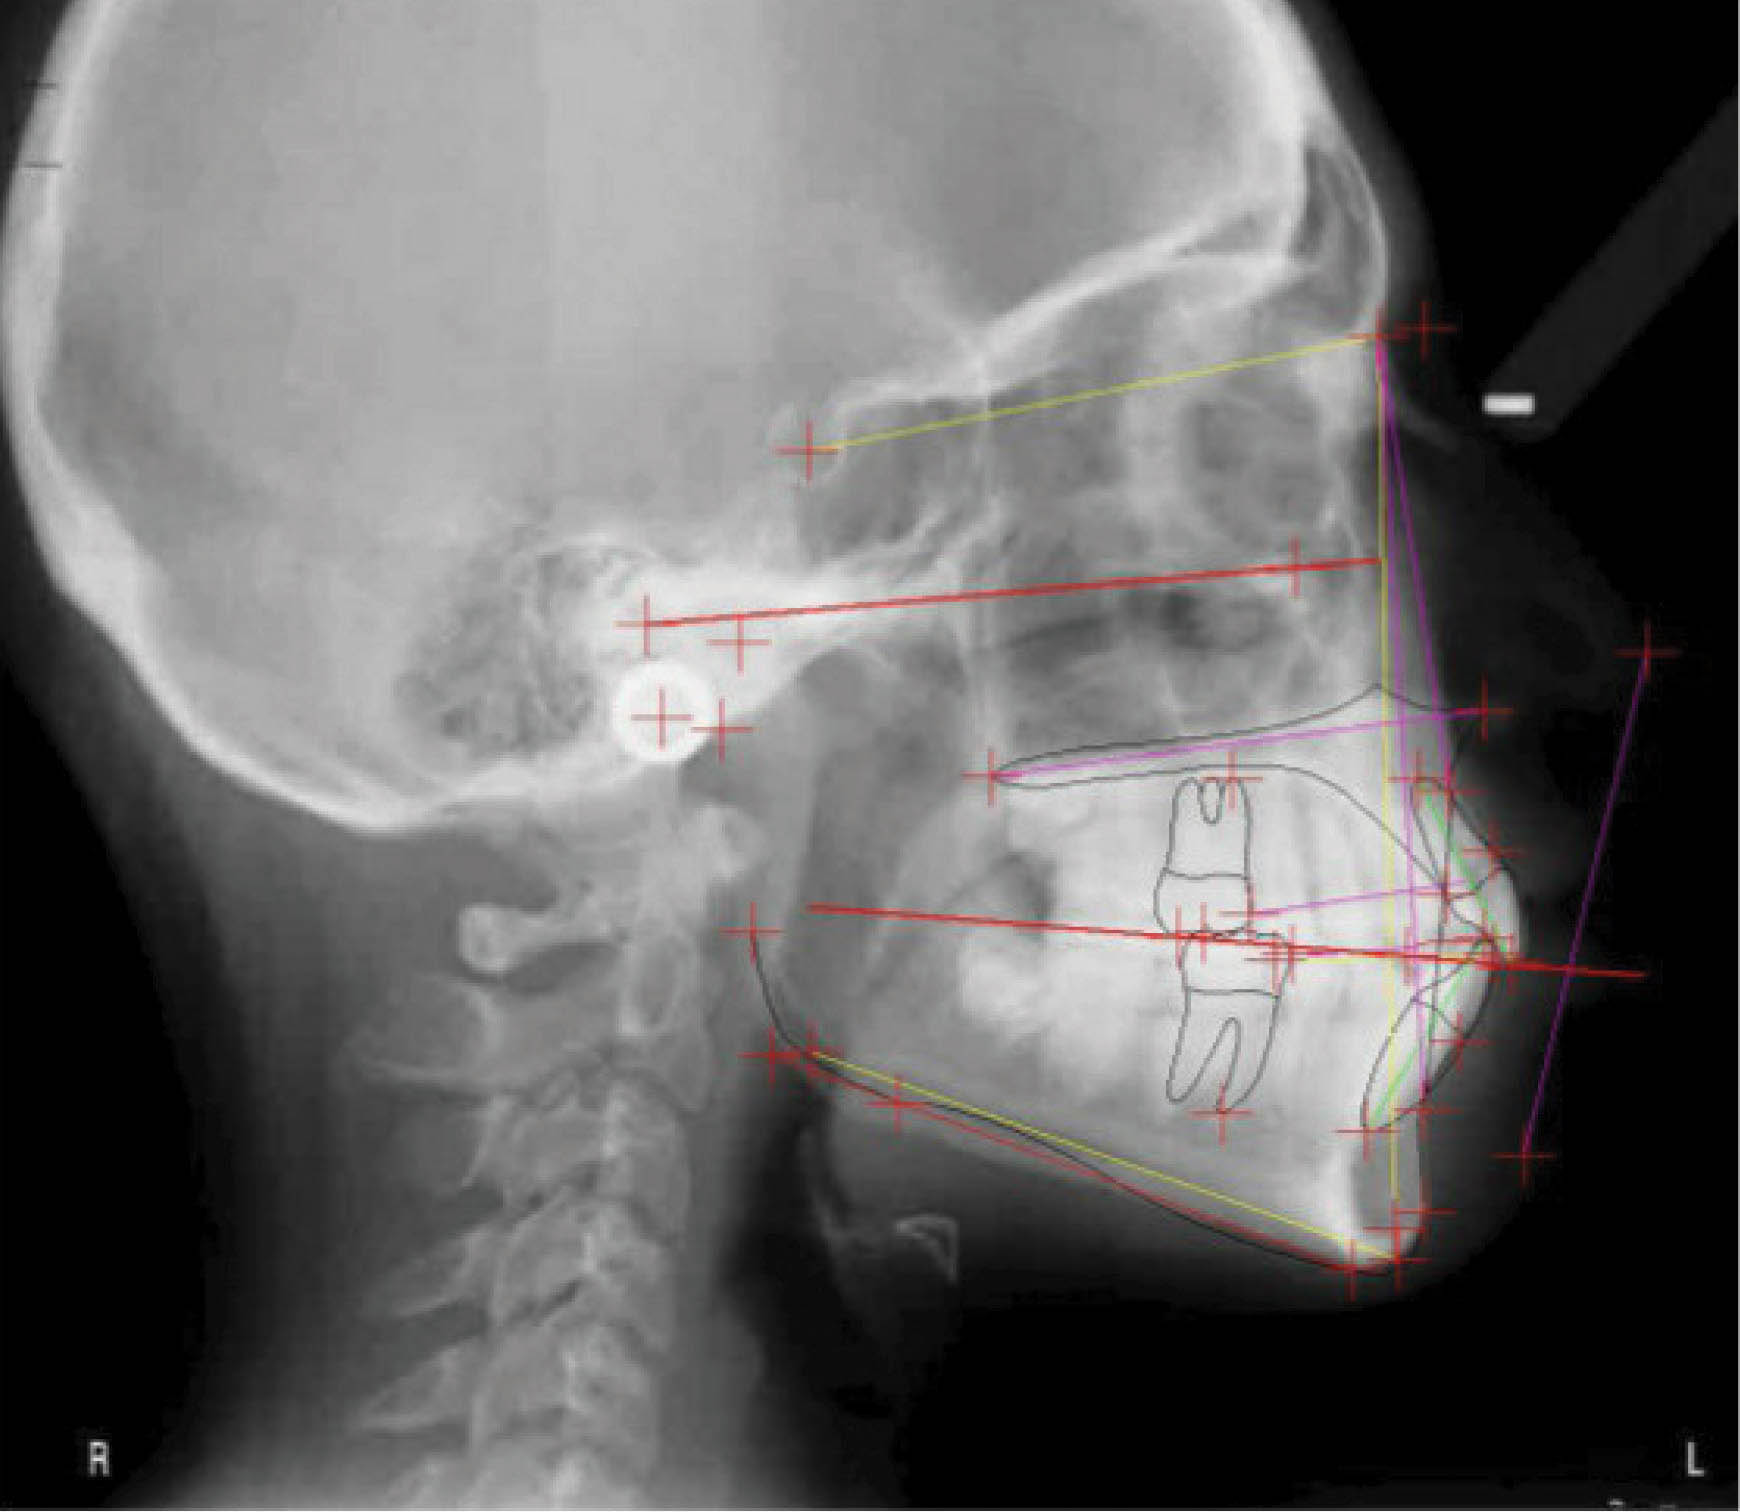

با سوپرایمپوز کردن لترال سفالومتری در شکل 35-6 شاهد سه درجه پروترود شدن انسیزورهای پایین هستیم. ارتفاع عمودی ثابت ماند و کنترل خوبی در حفظ زاویه پلن مندیبل داشتهایم. رادیوگرافی OPG پایان کار (شکل 36-6) طبیعی است. مدت نگهدارنده ۳۰ ماه بود و همه چیز خوب حفظ شده است (شکل 37-6).

شکل 35-6